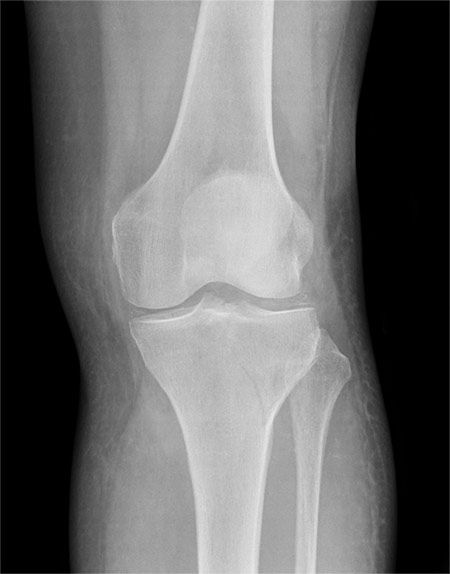

19 days

X-RAY QUIZ: Direct trauma to the lateral side of the knee. Is there a visible injury? If so, what is the injury? Start Quiz https://t.co/X7CYF8FOw0